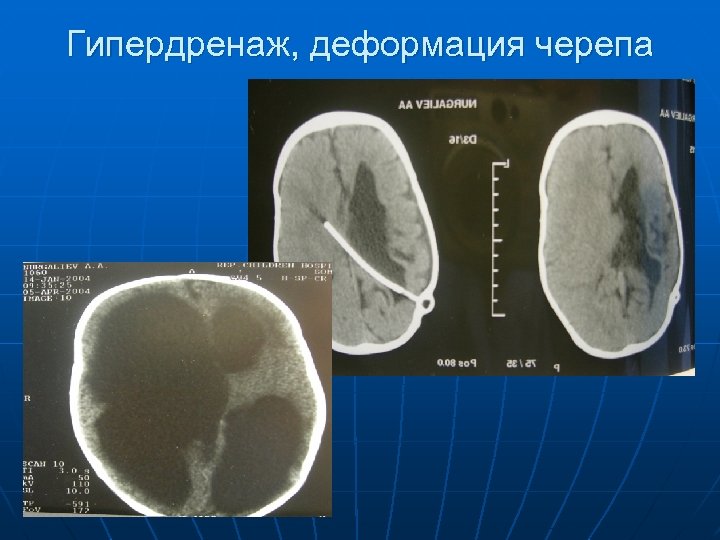

Гипердренаж, деформация черепа